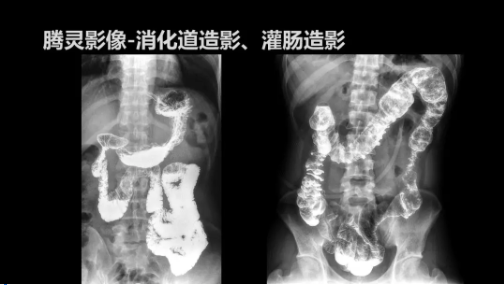

“騰靈”是安健科技的第四代動態(tài)DR產(chǎn)品,可實(shí)現(xiàn)全科室應(yīng)用。如各類常規(guī)的X線檢查、消化道檢查、骨科檢查、婦科、兒科檢查等。此外,安健科技為“騰靈”在真正意義上實(shí)現(xiàn)多科室、多功能診斷進(jìn)行了多項(xiàng)針對性設(shè)計。

此外,“騰靈”為了能夠幫助醫(yī)生更快速、有效的定位病灶,還增加了多項(xiàng)精準(zhǔn)診斷保障功能,如支持動態(tài)觀察診斷,實(shí)時高清點(diǎn)片等。“騰靈”透視切換高清點(diǎn)片曝光,捕捉關(guān)鍵病灶診斷僅需0.8s,同時還支持圖像局部放大,醫(yī)生可自由切換15’12’和9’三種放大模式,另外,“騰靈”還支持視頻保存、回放功能,幫助醫(yī)生在檢查結(jié)束后通過回放查看細(xì)節(jié),為醫(yī)生的診斷增加信心。